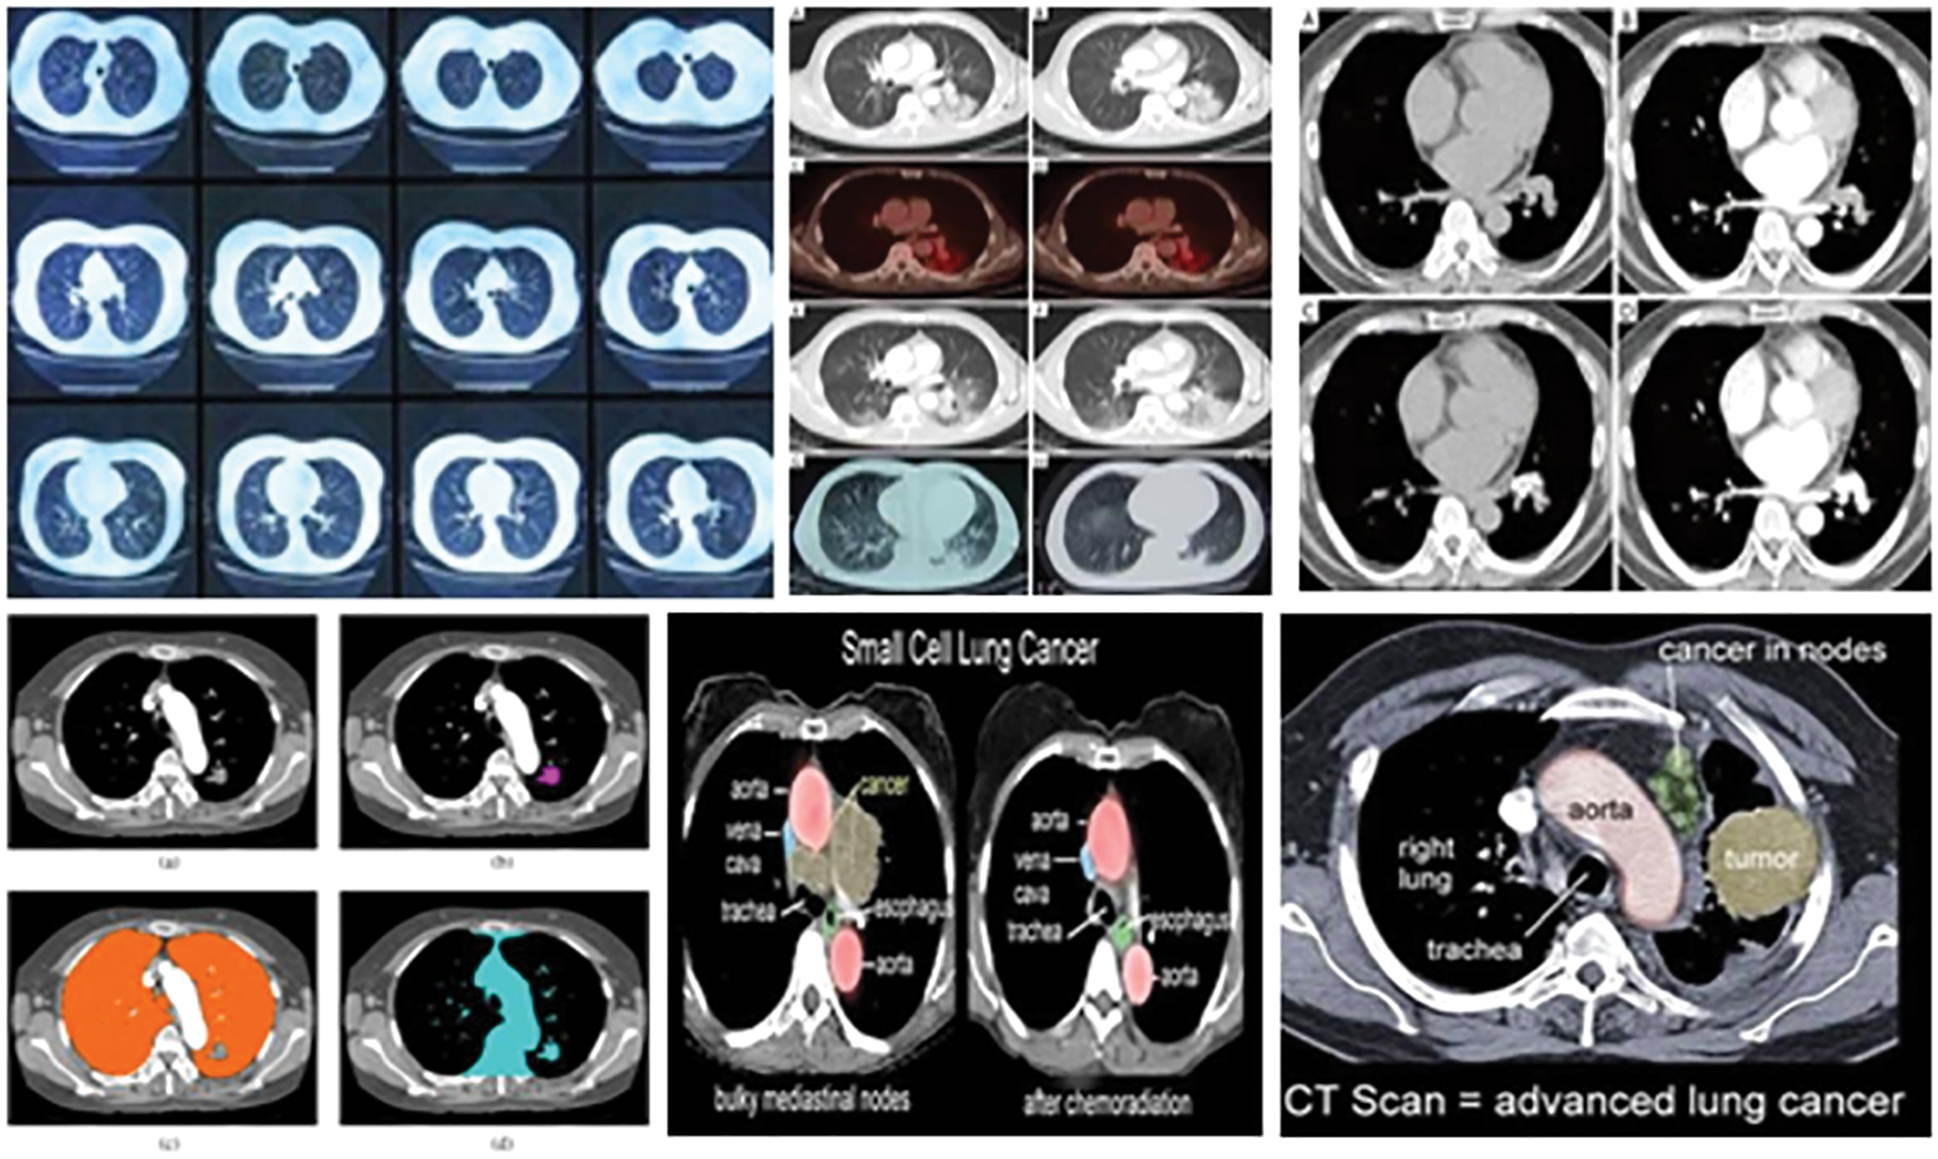

Cancer disease is a deadliest disease cause more dangerous one. By identifying the disease through Artificial intelligence to getting the mage features directly from patients. This paper presents the lung knob division and disease characterization by proposing an enhancement calculation. Most of the machine learning techniques failed to observe the feature dimensions leads inaccuracy in feature selection and classification. This cause inaccuracy in sensitivity and specificity rate to reduce the identification accuracy. To resolve this problem, to propose a Chicken Sine Cosine Algorithm based Deep Belief Network to identify the disease factor. The general technique of the created approach includes four stages, such as pre-processing, segmentation, highlight extraction, and the order. From the outset, the Computerized Tomography (CT) image of the lung is taken care of to the division. When the division is done, the highlights are extricated through morphological factors for feature observation. By getting the features are analysed and the characterization is done dependent on the Deep Belief Network (DBN) which is prepared by utilizing the proposed Chicken-Sine Cosine Algorithm (CSCA) which distinguish the lung tumour, giving two classes in particular, knob or non-knob. The proposed system produce high performance as well compared to the other system. The presentation assessment of lung knob division and malignant growth grouping dependent on CSCA is figured utilizing three measurements to be specificity, precision, affectability, and the explicitness.Keywords